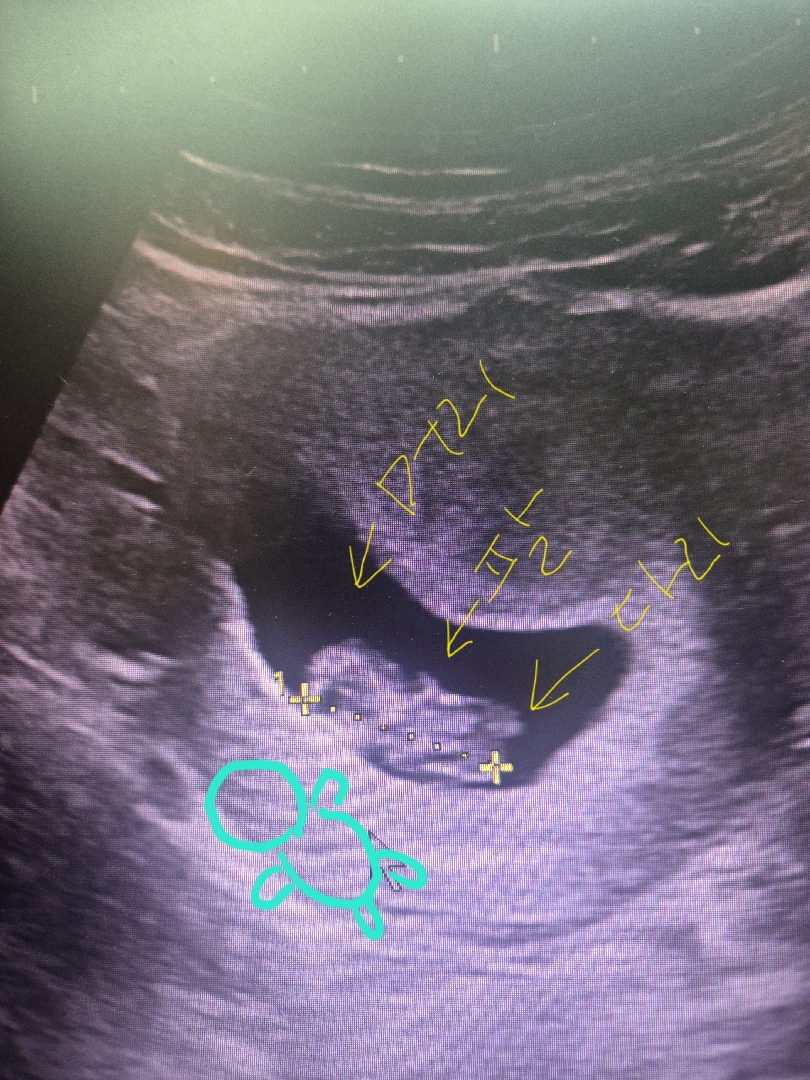

9주2일차 젤리곰 입성~!

ㅋㅋ젤리곰 합성이 어려워서 제가한번 그려봤어욤